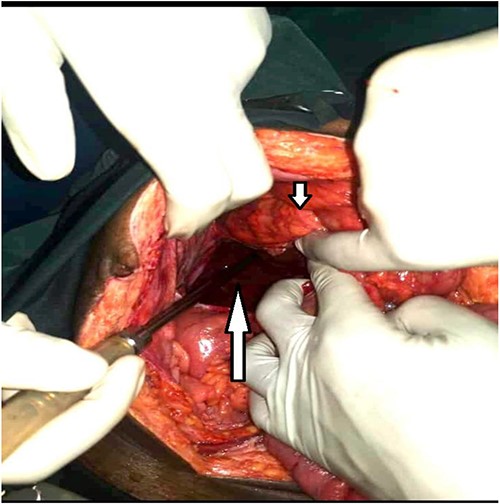

An exploratory laparotomy under general anesthesia was done. Intraoperatively, we found a large right retroperitoneal mass formed by a tuft of bowel that had herniated through a small tight (1.5 cm wide) opening just below the base of the cecum, creating a retroperitoneal pocket full of hemorrhagic fluid (~600 ml) and gangrenous ileum of ~30 cm, cecum and appendix. There was an associated ileal perforation ~15 cm from the ileocecal junction (Fig. 2). The gangrenous bowel loop was resected and an end-to-end, ileo-ascending, single-layered, hand-sewn anastomosis was done. The retroperitoneal pouch was lavaged with warm saline and was then closed over a tube drain. On inspection of the rest of the intra-abdominal contents, a rectal tumor was found with the dilated descending and sigmoid colon, but no extra-serosal, adjacent nor obvious distant organ metastasis. A pre-emptive diversion loop sigmoidostomy was done and the abdomen was closed in layers. Post-operatively: the patient was kept on intravenous piperacillin/tazobactam, metronidazole, morphine and paracetamol, kabiven and crystalloid fluids. Enteral feeds were gradually re-introduced, starting with clear fluids on the second post-operative day, and the patient was taught colostomy self-care. He recovered steadily without major post-operative complications and was discharged on Day 4 post-operatively through the Cancer Institute for re-evaluation for more cycles of neo-adjuvant chemotherapy before scheduling him for a low anterior resection.

Large retroperitoneal paracecal pouch (long arrow) and the cecum above it (short arrow).